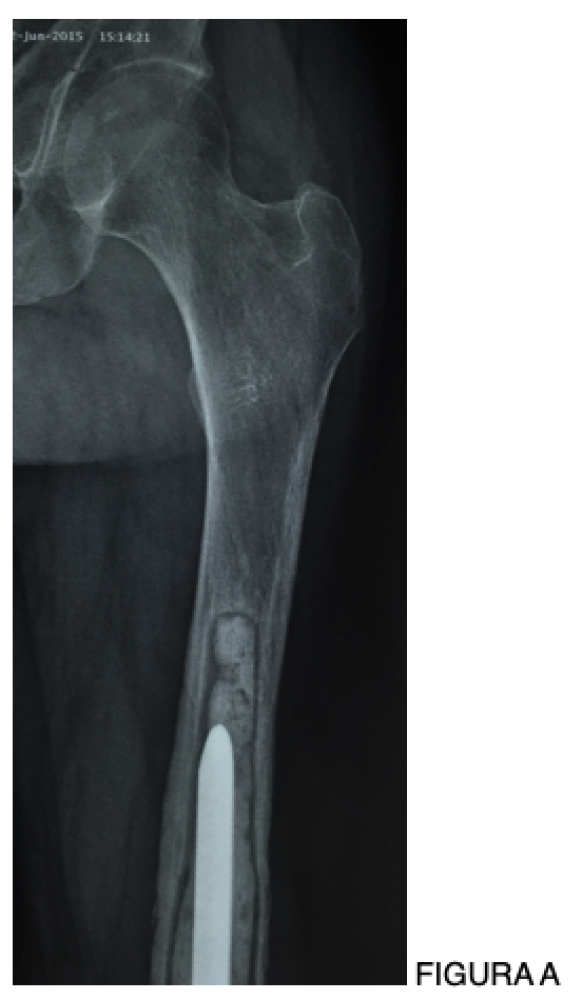

Seja nas artroplastias do quadril, joelho, ombro e tornozelo, seja nas endopróteses utilizadas no tratamento dos tumores ósseos, considero a infecção a complicação mais difícil de ser resolvida na Ortopedia.

Na Ortopedia Oncológica, esse cenário torna-se ainda mais dramático. Não raramente, o desfecho final de uma infecção profunda e refratária é a amputação, com impacto devastador para o paciente e para a equipe médica. Apesar disso, os princípios do tratamento da infecção são comuns a todos nós, independentemente da articulação envolvida ou da indicação original da prótese: profilaxia adequada, diagnóstico preciso, decisão cirúrgica correta e manejo criterioso da antibioticoterapia.

• Próteses não convencionais e oncológicas: incidência entre 10% e 25%, com maior gravidade clínica e impacto funcional [4,6].